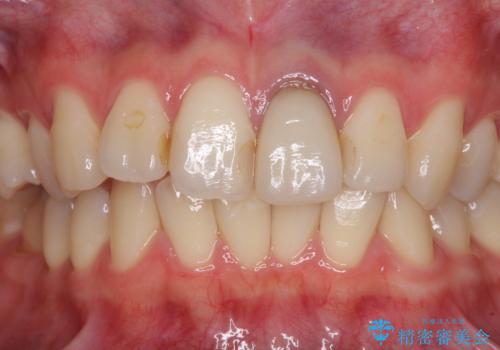

- 前歯のクラウン付近の歯肉が黒く見えることを気にして来院された患者様です。

根管治療を行った後に、オールセラミッククラウンにて補綴することとしました。

オーダーメイドタイプのクラウンを選択いただいたので、まるで天然の歯と見間違うほど自然に仕上がり、患者様には大変満足していただきました。